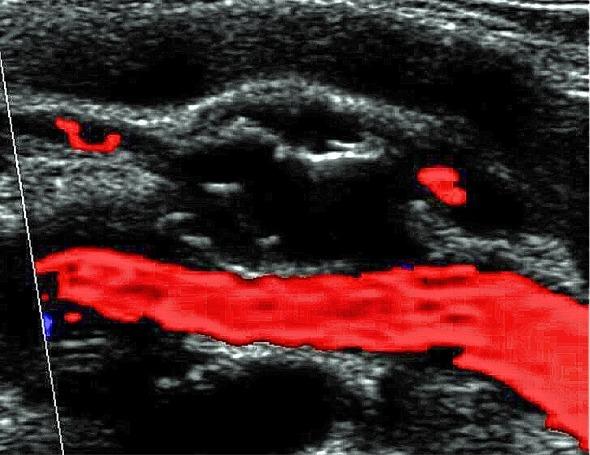

Adventitial cystic disease of the popliteal artery is an uncommon pathology that should be considered in differential diagnostic of younger patients with intermittent claudication and without risk factors for peripheral atherosclerotic arterial disease. We report the case of a 51 year-old male patient presenting with lower-limb intermittent claudication in whom this pathology was diagnosed and who was treated with segmental arterial resection and autologous saphenous vein interposition. We also discuss diagnostic and therapeutic alternatives.

腘动脉外膜囊肿性疾病是一种罕见的病理学情况,在诊断较年轻的间歇性跛行且无外周动脉粥样硬化性疾病危险因素的患者时应予以考虑。我们报告一例51岁男性患者,其因下肢间歇性跛行就诊,被诊断为此种疾病,并接受了节段性动脉切除及自体大隐静脉移植术治疗。我们还讨论了诊断和治疗的其他选择。